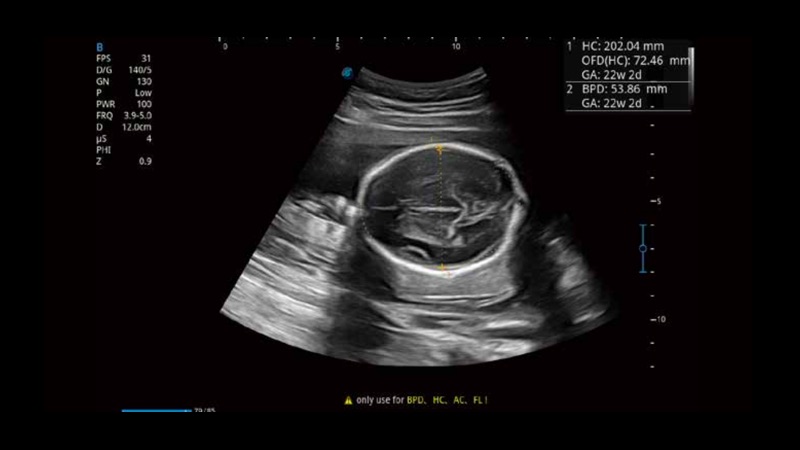

S-Fetus基于大数据深度学习算法,能够帮助您在产前筛查过程中智能识别胎儿标准切面、自动测量并录入报告。一个按键,即可智能、精准、高效地获取胎儿生理指标,极大简化您的产科检查操作。

可快速对产科扫查切面完成胎儿生理学参数的自动测量,减少操作者按键次数,大幅提升检查效率。